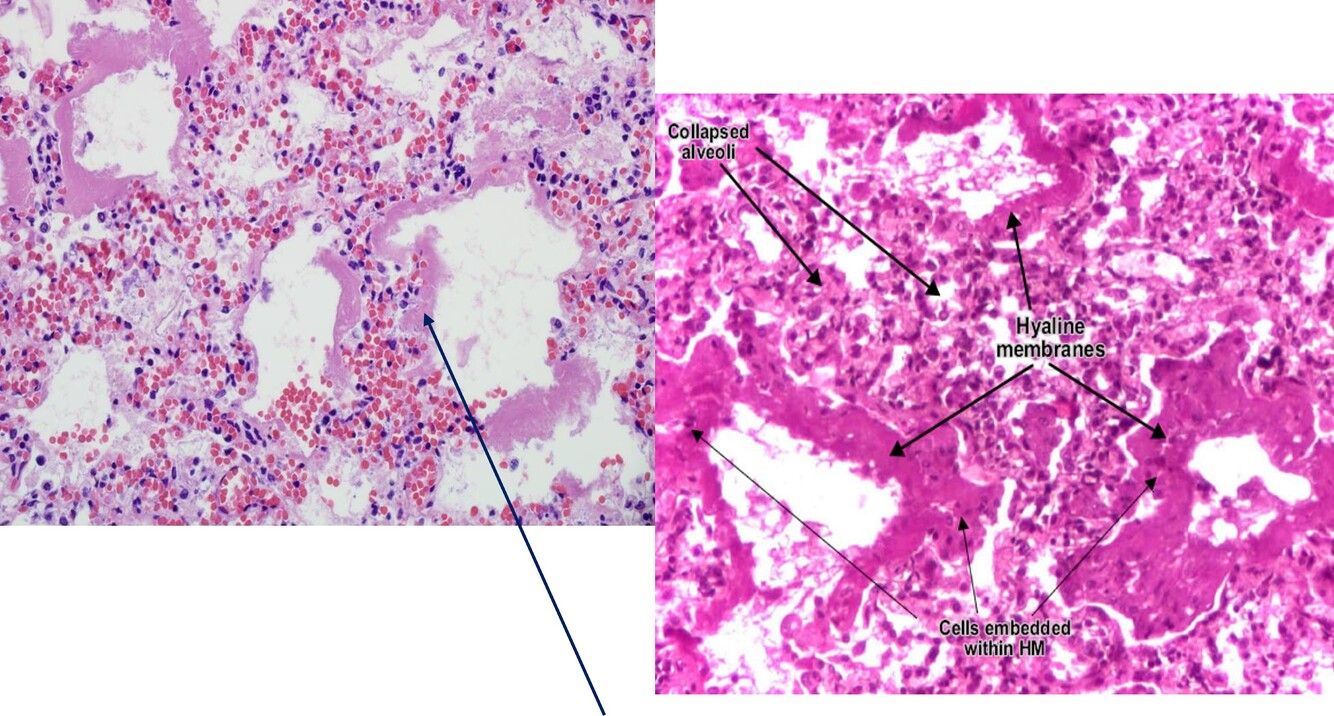

The respiratory membranes (bronchioles, alveolar ducts, & alveoli) are made up of eosinophilic hyaline, fibrin, & cell debris with necrotic type pneumocytes

Neonatal respiratory distress syndrome/ hyaline membrane disease

Eonsinophilic Hyaline Membranes line the alveolar ducts and alveoli, made up of fibrin admixed with cell debris (necrotic type II pneumocytes) 🡪 Increased pulmonary vascular permeability, plasma leaks into the alveoli, which makes hyaline stain pink.

: Neonatal Respiratory Distress Syndrome / Hyaline Membrane Disease